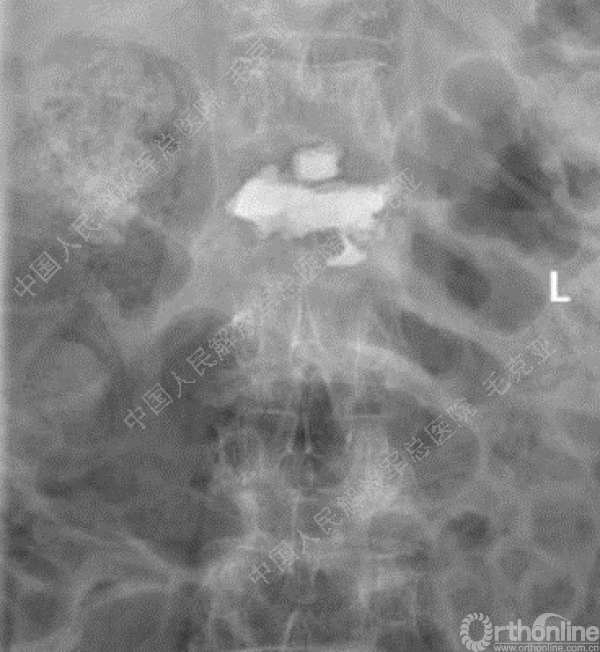

导语:随着社会老龄化的不断加速,骨质疏松性椎体压缩骨折作为一种普遍存在的老年骨科疾病已经成为现今骨科界的一个热点话题。传统的保守疗法治疗效果不佳,而现有的椎体增强技术又具有多种风险和缺陷。针对这种现状,中国人民解放军总医院毛克亚教授提供了一种新的解决方法。